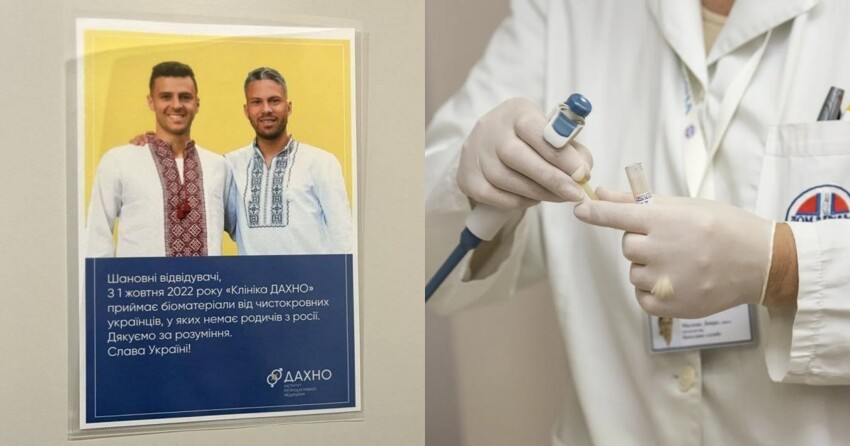

Особенно эпично при этом выглядит листовка с объявлением, на котором красуются "щирые" украинцы пан Жуниор Мораес и пан Марлос Ромеро Бонфин.

Пиво безалкогольное, женщины резиновые, вот и детей из пробирок собираются клепать. Японцы они такие...